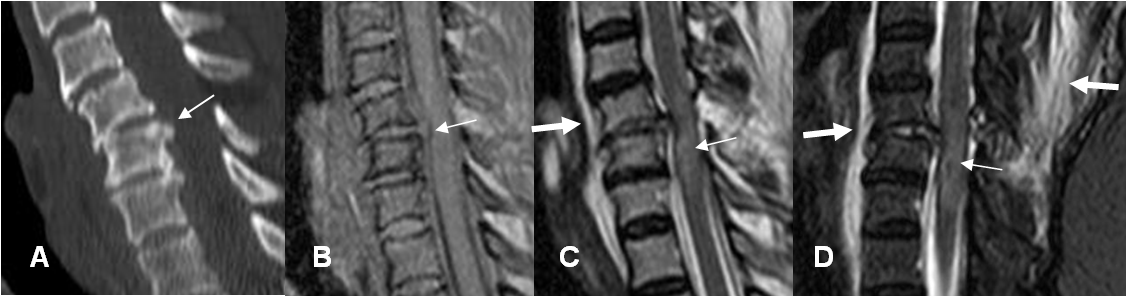

Fig 178. Lesión medular mixta.

A: RM sagital en T1. Fractura vertebral inestable, con fragmento retropulsado. No se detecta alteración en la señal medular.

B: RM sagital en T2. Area de edema medular hiperintensa (Flecha delgada) y otra de sangrado agudo hipointensa. (Flecha gruesa). Existe colección prevertebral.

Fig 179. Sangrado medular.

A: RM sagital en T2 y B: RM sagital en GE. Lesión medular hiperintensa en T2 e hipointensa en GE, por contusión hemorrágica.

Fig 180 A. Lesión medular mixta.

A: RM sagital en T2 y B: RM sagital en STIR. Paciente con canal estrecho y trauma en hiperflexión. Se aprecia la medula engrosada e hiperintensa entre C3 y C6, por edema.

C: RM sagital en GE. En la zona central hay area lineal, hiperintensa en T2 e hipointensa en GE, sugestivas de sangrado.